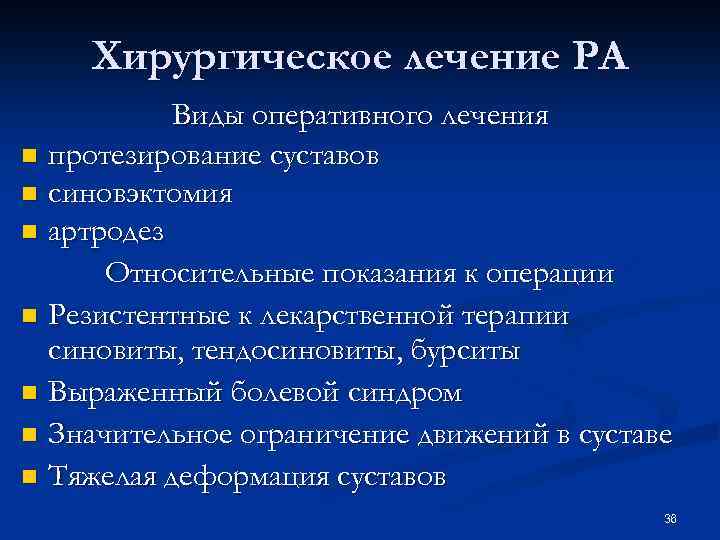

Хирургическое лечение РА Виды оперативного лечения n протезирование суставов n синовэктомия n артродез Относительные показания к операции n Резистентные к лекарственной терапии синовиты, тендосиновиты, бурситы n Выраженный болевой синдром n Значительное ограничение движений в суставе n Тяжелая деформация суставов 36

Хирургическое лечение РА Виды оперативного лечения n протезирование суставов n синовэктомия n артродез Относительные показания к операции n Резистентные к лекарственной терапии синовиты, тендосиновиты, бурситы n Выраженный болевой синдром n Значительное ограничение движений в суставе n Тяжелая деформация суставов 36